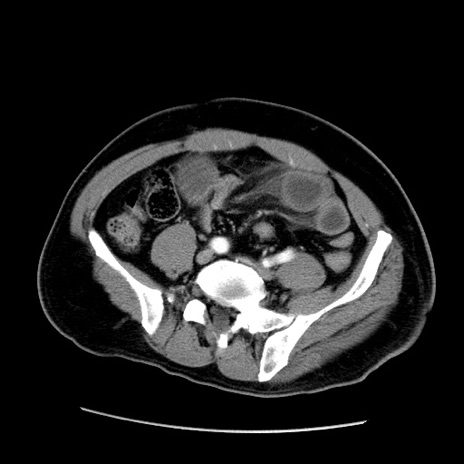

冠状断像